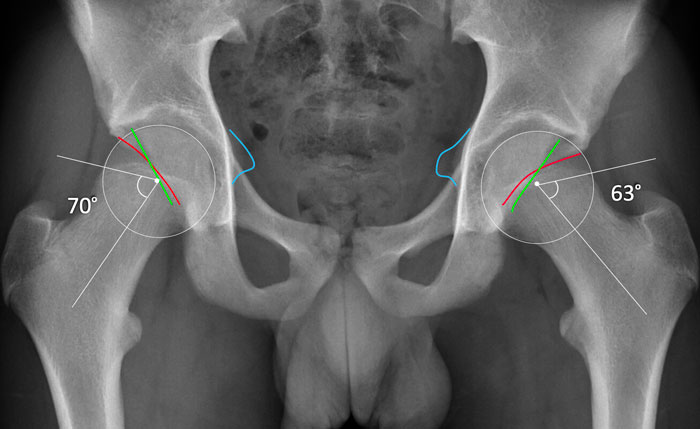

W-CEA

W-CEA là góc giữa đường thẳng đứng đi qua tâm chỏm xương đùi và đường thẳng đến bờ ngoài của vòm ổ cối, đây là vùng chịu lực và đặc của phần trên ổ cối.

Góc này đại diện cho độ che phủ phần trên-trước, có liên quan nhiều hơn đến FAI.

L-CEA

L-CEA là góc trung tâm-cạnh bên, được đo đến bờ ổ cối ngoài xa và đại diện cho độ che phủ trên-ngoài.

Đôi khi các phép đo này trùng nhau.

Góc trung tâm-mép (CEA)

Khi đo góc trung tâm-mép (CEA), cần sử dụng ranh giới ngoài của thành trước-trên/bờ ngoài của vòm ổ cối, còn được gọi là góc trung tâm-mép ngoài của Wiberg/W-CEA.

Trên phim X-quang thẳng (AP), có thể xác định điểm này bằng cách sử dụng bờ ngoài của vùng xơ cứng dưới sụn của ổ cối phía trên.

Khi sử dụng bờ ngoài cùng của ổ cối (thường phản ánh bờ của ổ cối trên-ngoài hơn là bờ trước-trên), hay còn gọi là L-CEA, mức độ che phủ có thể bị đánh giá quá cao.

Nếu có tình trạng ngả sau của ổ cối (phần trên), W-CEA và L-CEA có thể bằng nhau.

Nếu góc này bằng hoặc lớn hơn 40 độ, nó được phân loại là

pincer toàn cầu với độ che phủ quá mức của chỏm xương đùi.

Kiểu kẹp gọng kìm đơn thuần hai bên (chỉ có hình chụp tư thế AP) với góc W-CEA tăng và dấu hiệu gai ngồi ở bệnh nhân nữ 16 tuổi, đến khám vì các triệu chứng liên quan đến khớp háng.